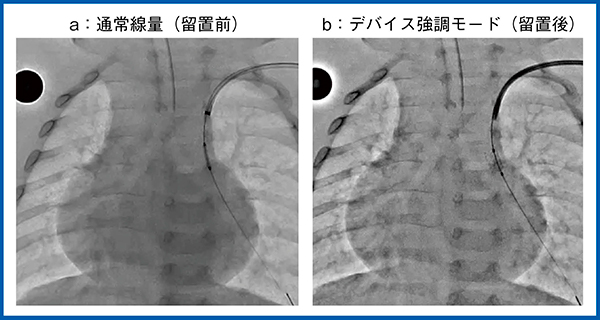

図2は,経皮的心房中隔欠損閉鎖術(Amplatzer Septal Occluder:ASO治療)におけるwiggleによるデバイスの安定性の確認の様子であるが,デバイス強調モード(b)ではきわめて明瞭に描出されている。

図2 デバイス強調モード:ASO治療